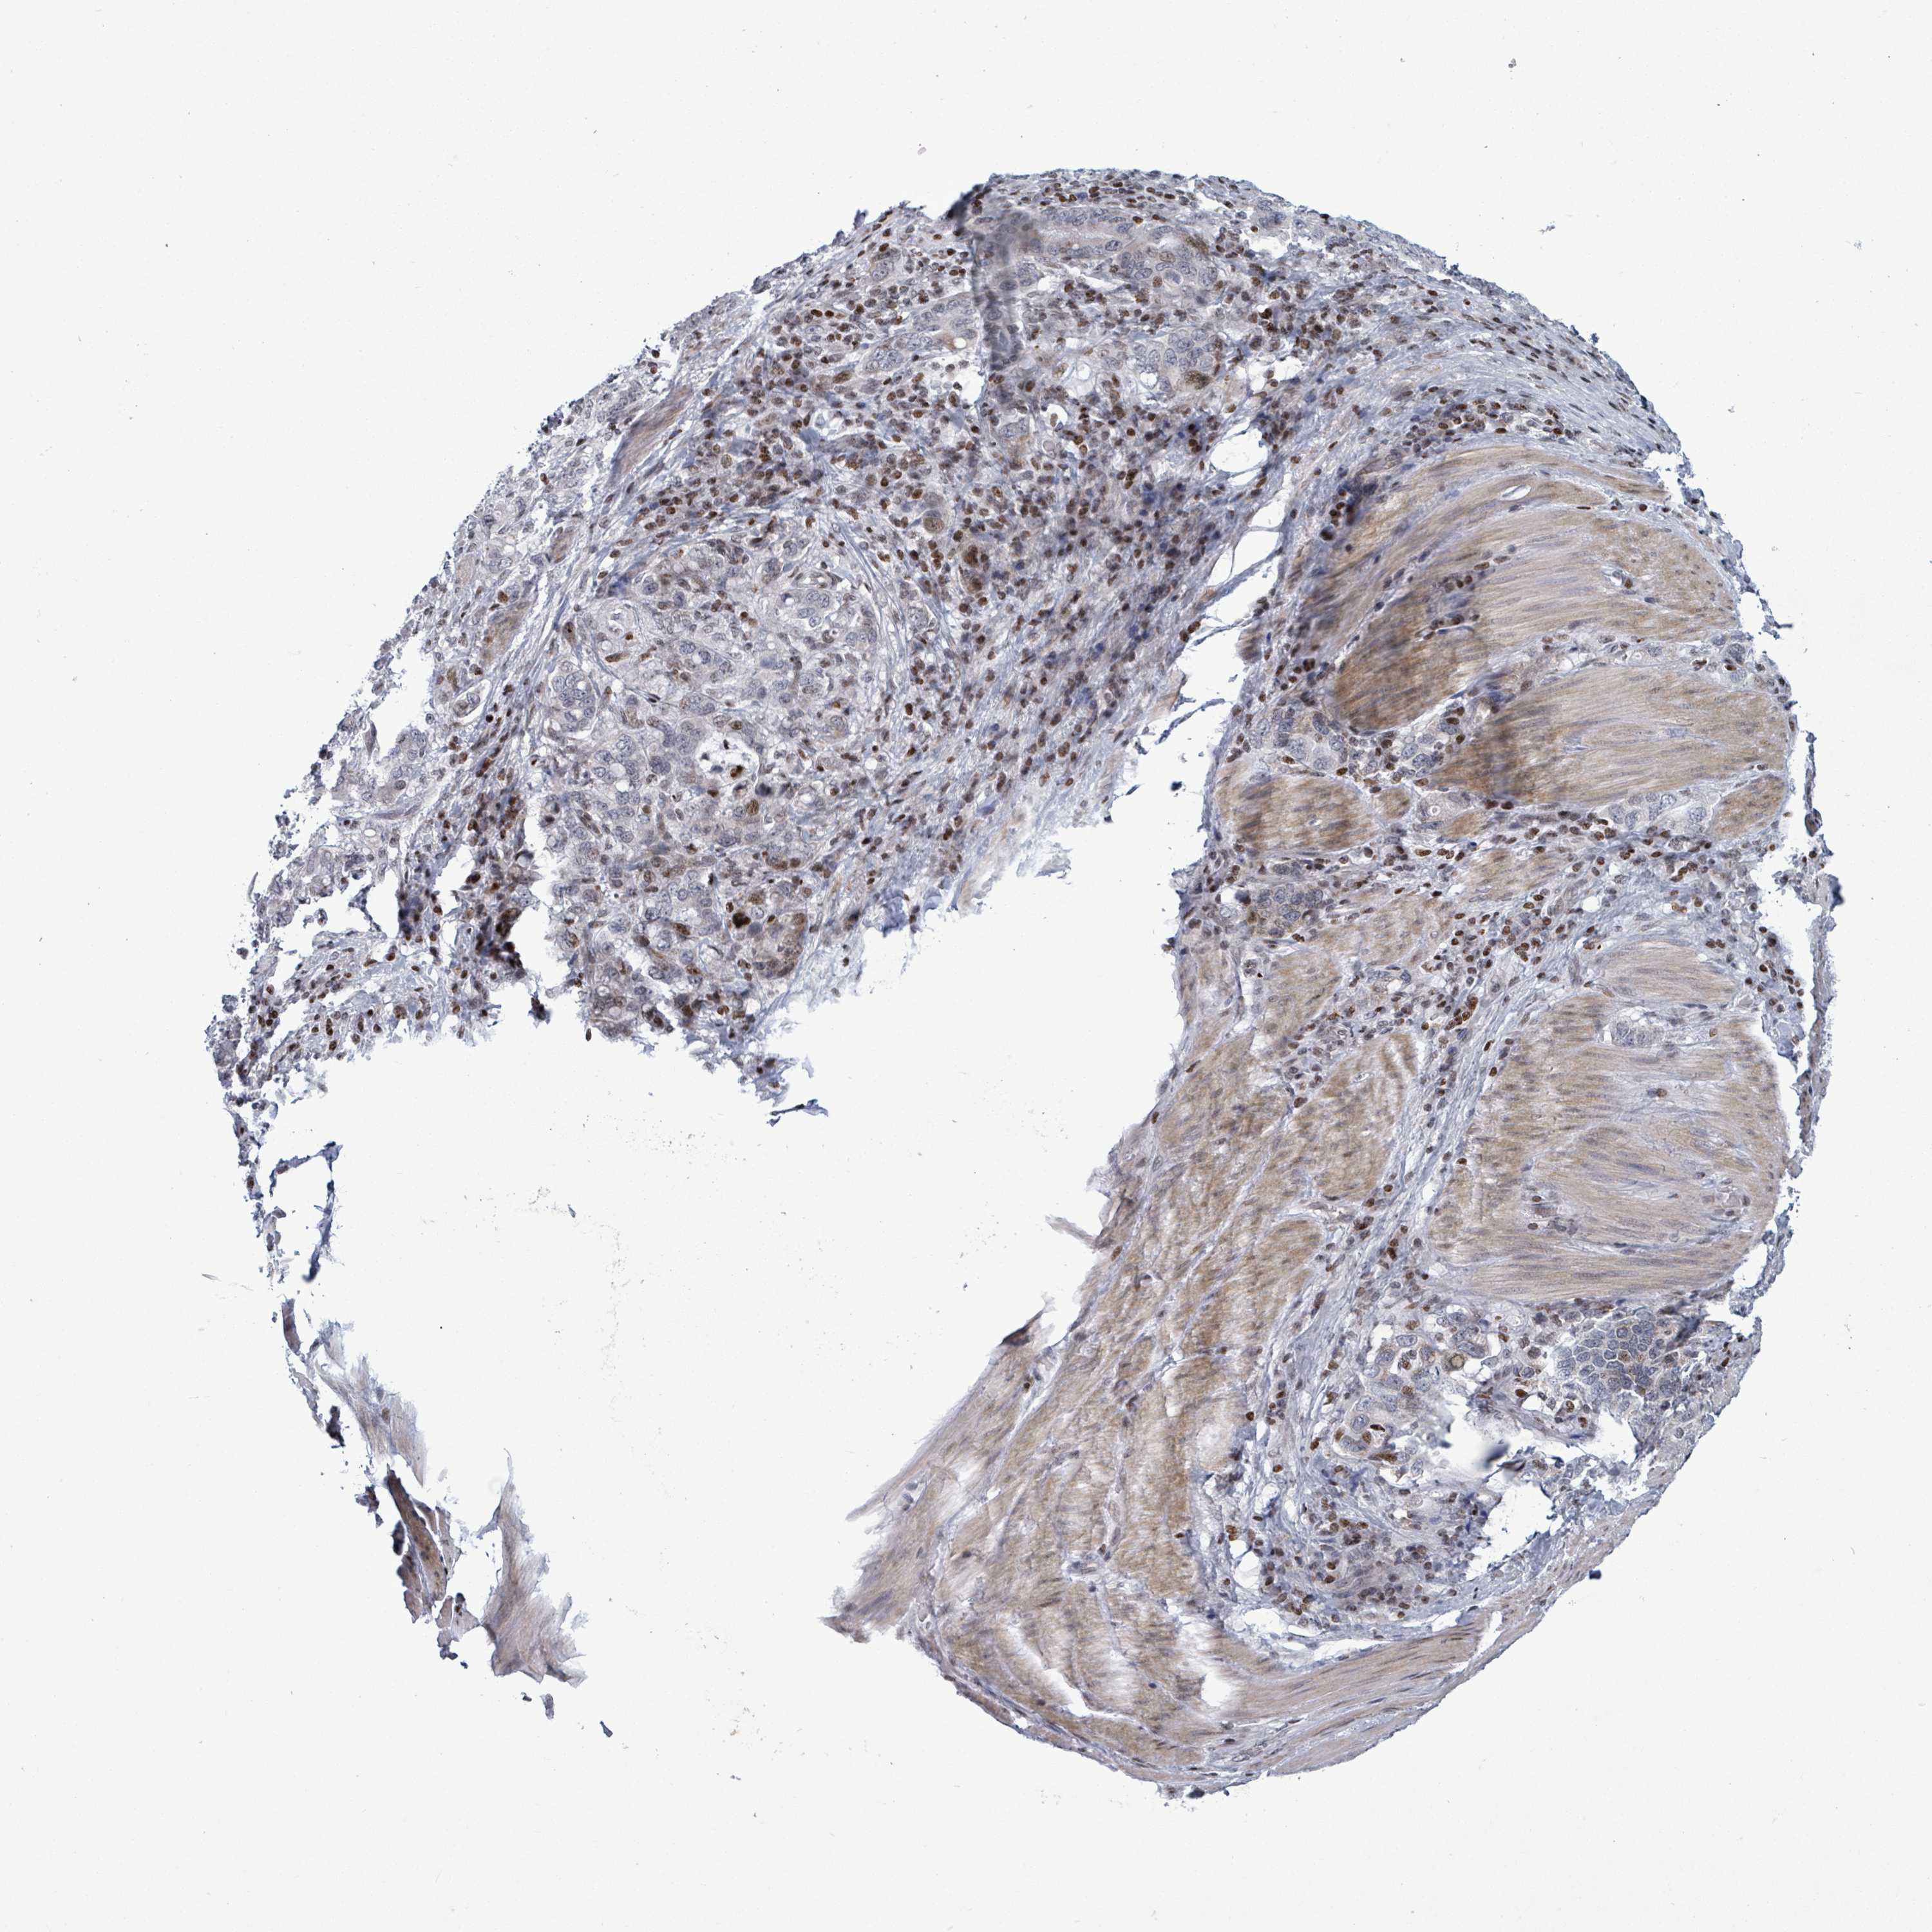

STOMACH CANCER - Protein expressioni

A mouse-over function shows sample information and annotation data. Click on an image to view it in a full screen mode. Samples can be filtered based on level of antibody staining by selecting one or several of the following categories: high, medium, low and not detected. The assay and annotation is described here.

Note that samples used for immunohistochemistry by the Human Protein Atlas do not correspond to samples in the TCGA dataset.

Antibody stainingi

Antibody staining in the annotated cell types in the current human tissue is reported as not detected, low, medium, or high, based on conventional immunohistochemistry profiling in selected tissues. This score is based on the combination of the staining intensity and fraction of stained cells.

Each image is clickable and will lead to virtual microscopy that enables deeper exploration of all samples and also displays staining intensity scores, fraction scores and subcellular localization as well as patient and tissue information for each sample.

Antibody HPA051804

Antibody HPA063581

Staining

High

Medium

Low

Not detected

Intensity

Strong

Moderate

Weak

Negative

Quantity

>75%

75%-25%

<25%

None

Location

Nuclear

Cytoplasmic/membranous

Cytoplasmic/membranous,nuclear

Adenocarcinoma, NOS